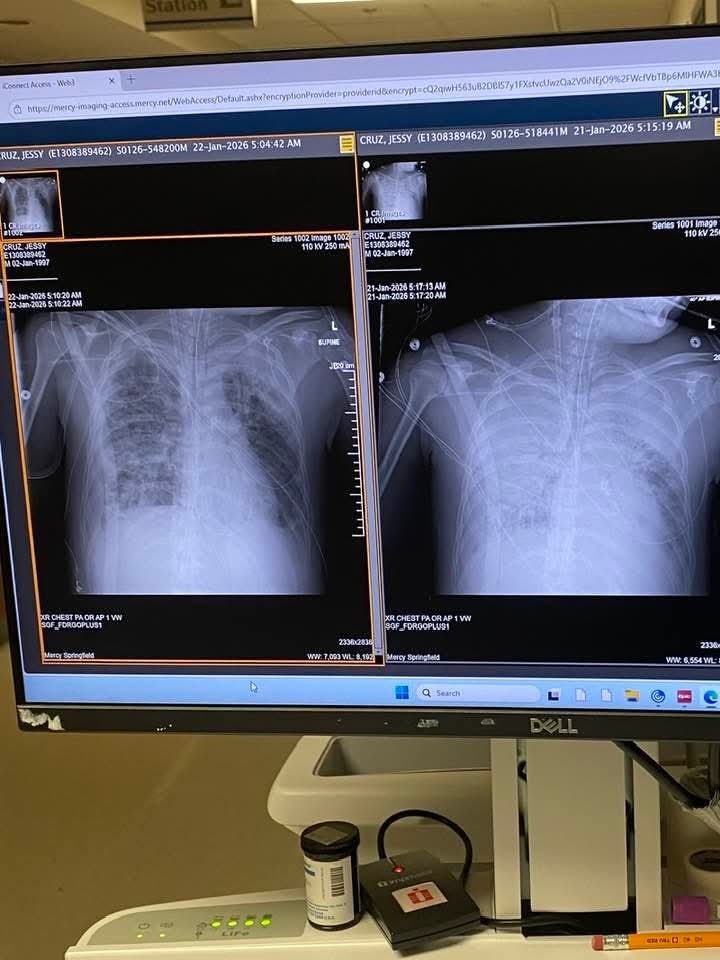

My son Jessy Cruz is currently in a rehabilitation hospital after a life-threatening incident that left his lungs collapsed and caused a stroke. He has been in the hospital for over three months, and now faces the difficult journey of relearning how to walk and manage daily life. This has been an incredibly challenging time for Jessy and our entire family, as we watch him fight to regain his strength and independence.